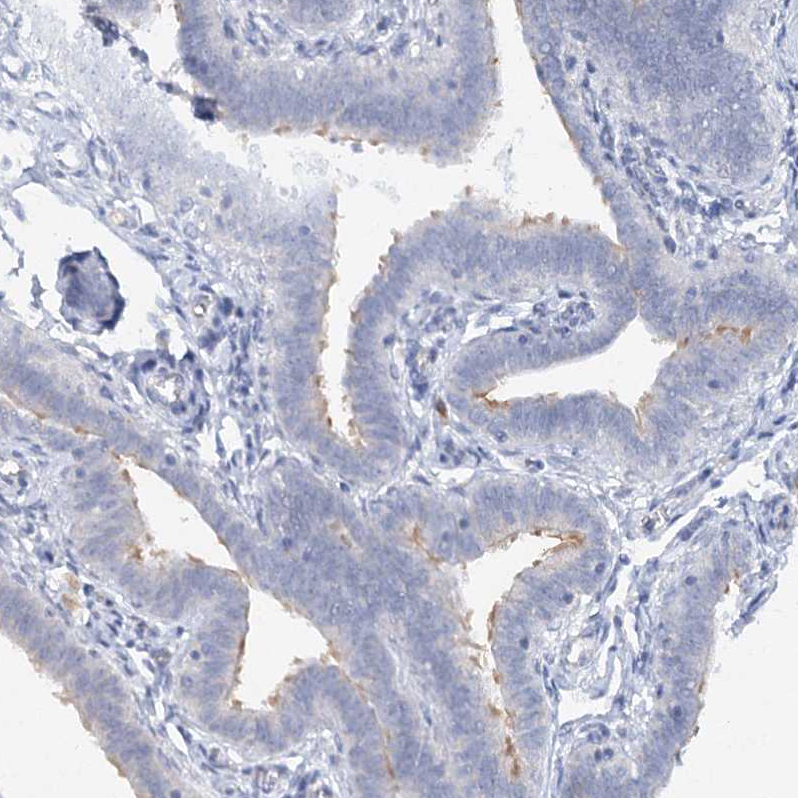

Immunohistochemical staining of human pancreas shows strong cytoplasmic positivity in islets of Langerhans.